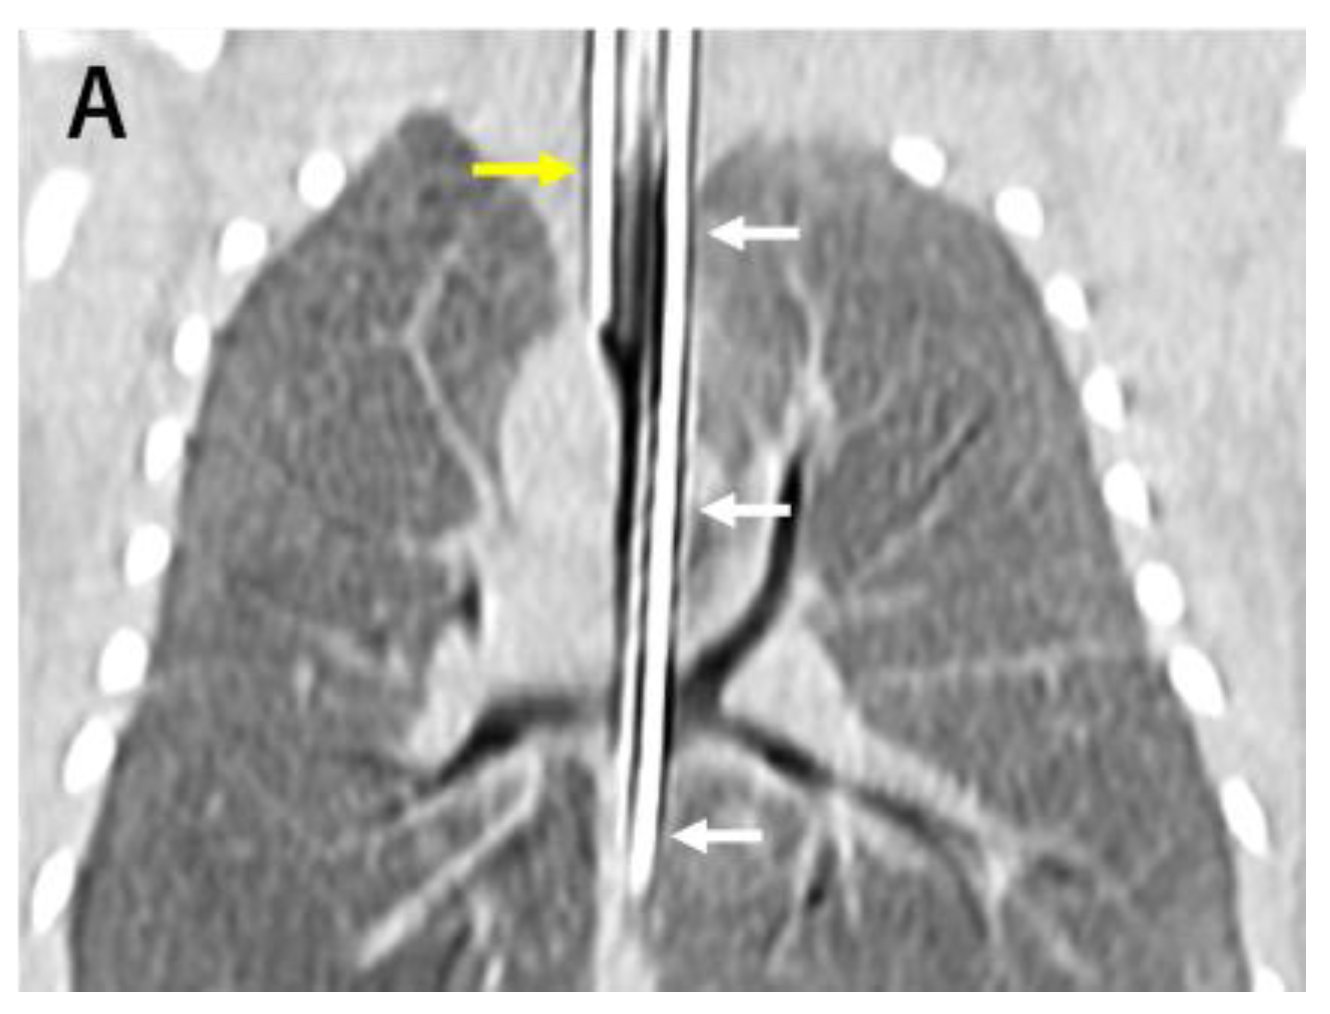

2. Case Description